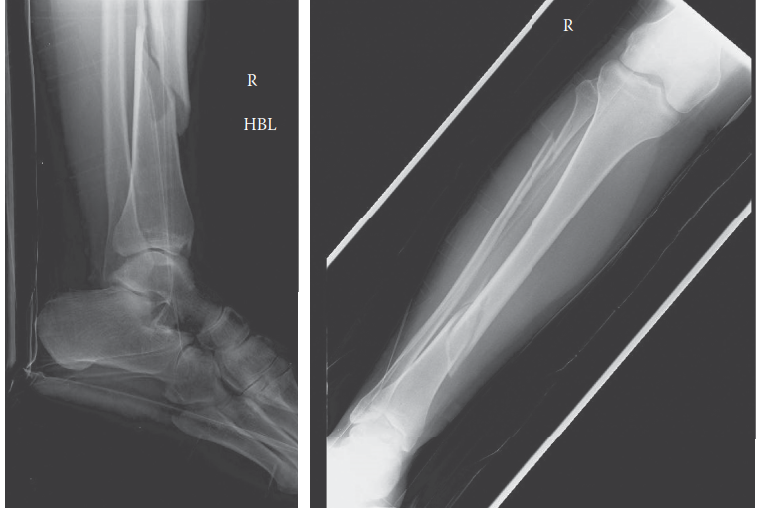

You are the on-call orthopaedic registrar and you are asked to see a young man who has been brought to the em…

Hit the Button to See Answer 1. Can you describe the radiographs? 2. What is responsible for the deformities …

1. Can you describe the radiographs 1. Can you describe the radiographs? ANSWER